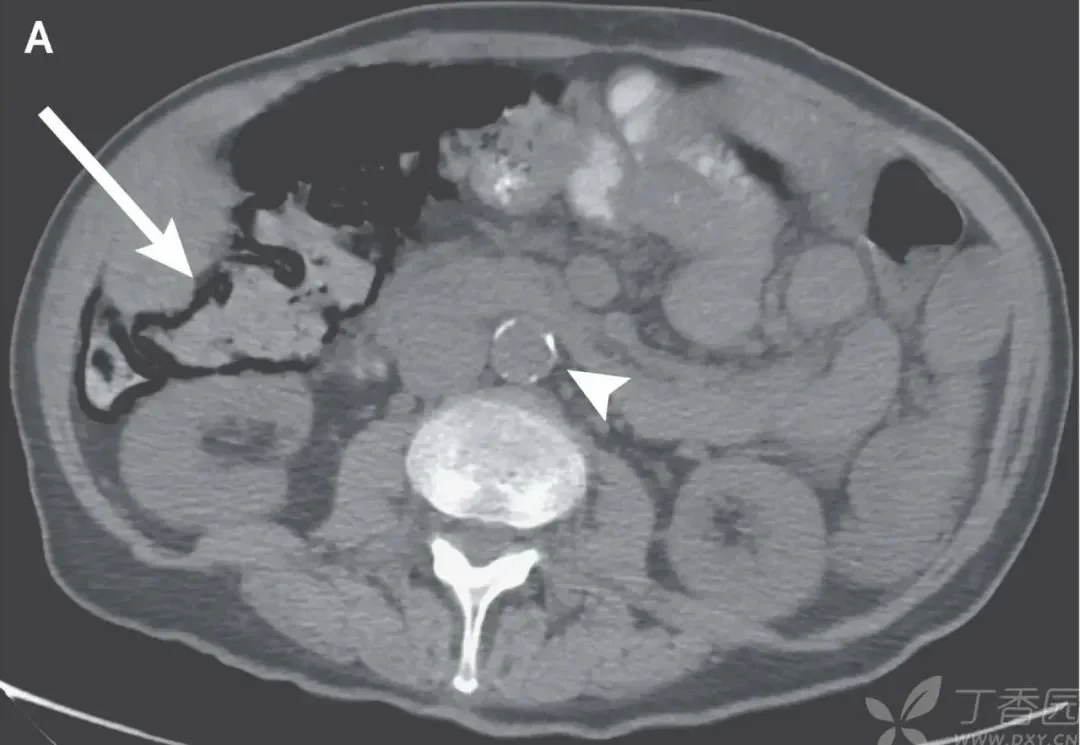

本次入院前一個月,患者因急性精神錯亂和水腫加重入院,并進行了右上腹超聲檢查,如下圖。

打開鳳凰新聞,查看更多高清圖片